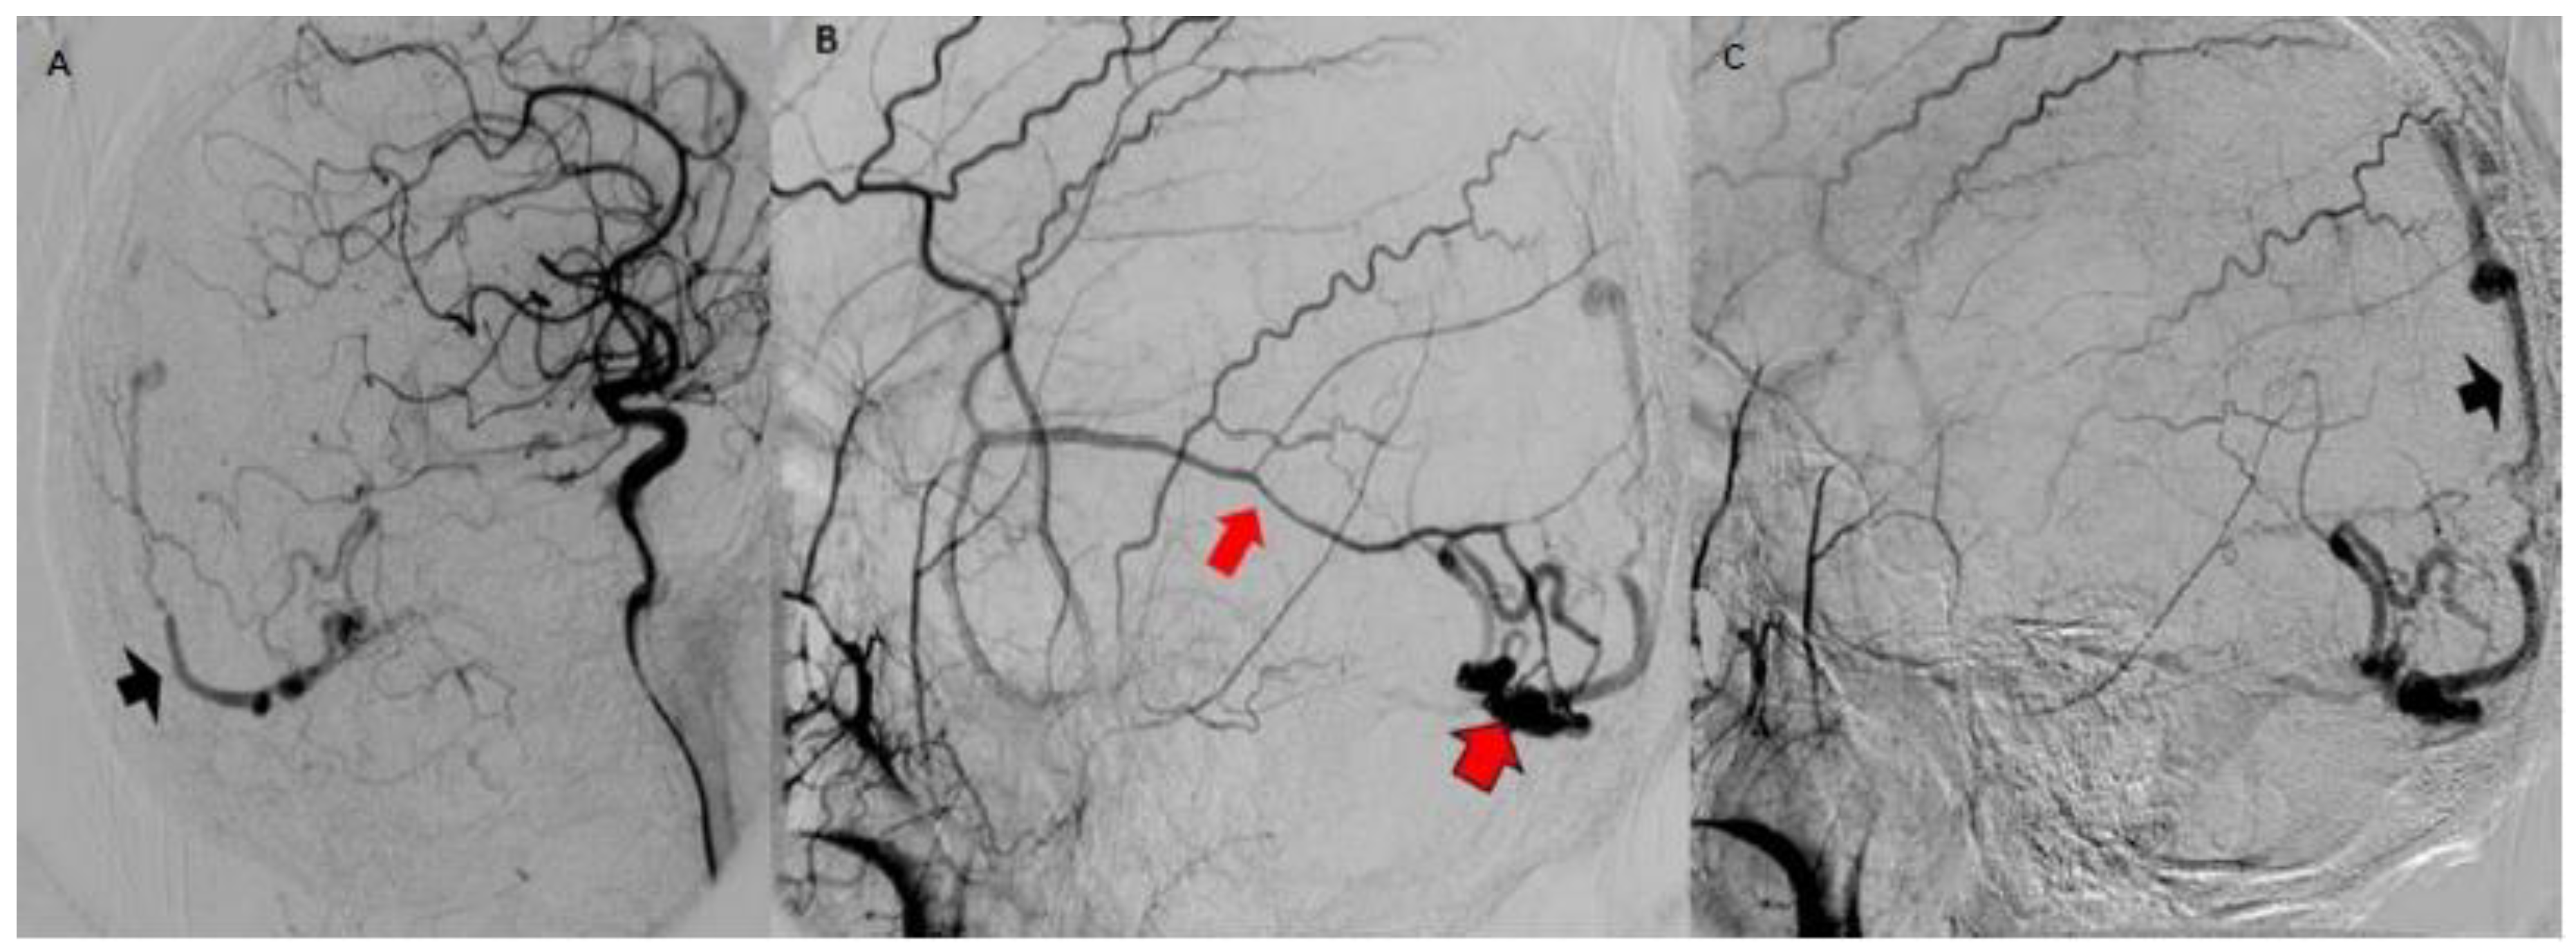

Figure 5.

Digital subtraction angiography. (A) branch of the external carotid is seen as the afferent vessel (red arrow in (B)) to the malformative nest (red arrow with black border in (B)) with a thick vein of early cortical drainage (black arrowheads in (A,C)) that goes to the longitudinal superior sinus.